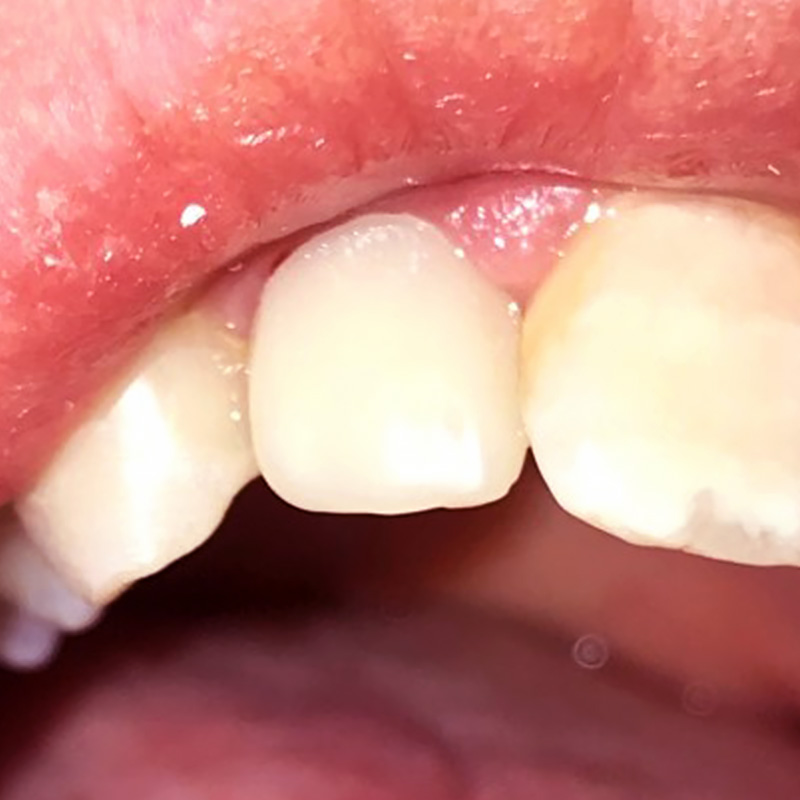

Установлена керамическая вкладка для укрепления зуба (первый этап). Изготовлена и установлена циркониевая коронка на 21 зуб (второй этап)Смотреть работуСрок лечения:2 неделиСумма лечения:35 000 р.

Повышение эстетических показателей путём установки циркониевой коронкиСмотреть работуСрок лечения:2 недели (в 2 этапа)Сумма лечения:35 000 руб.